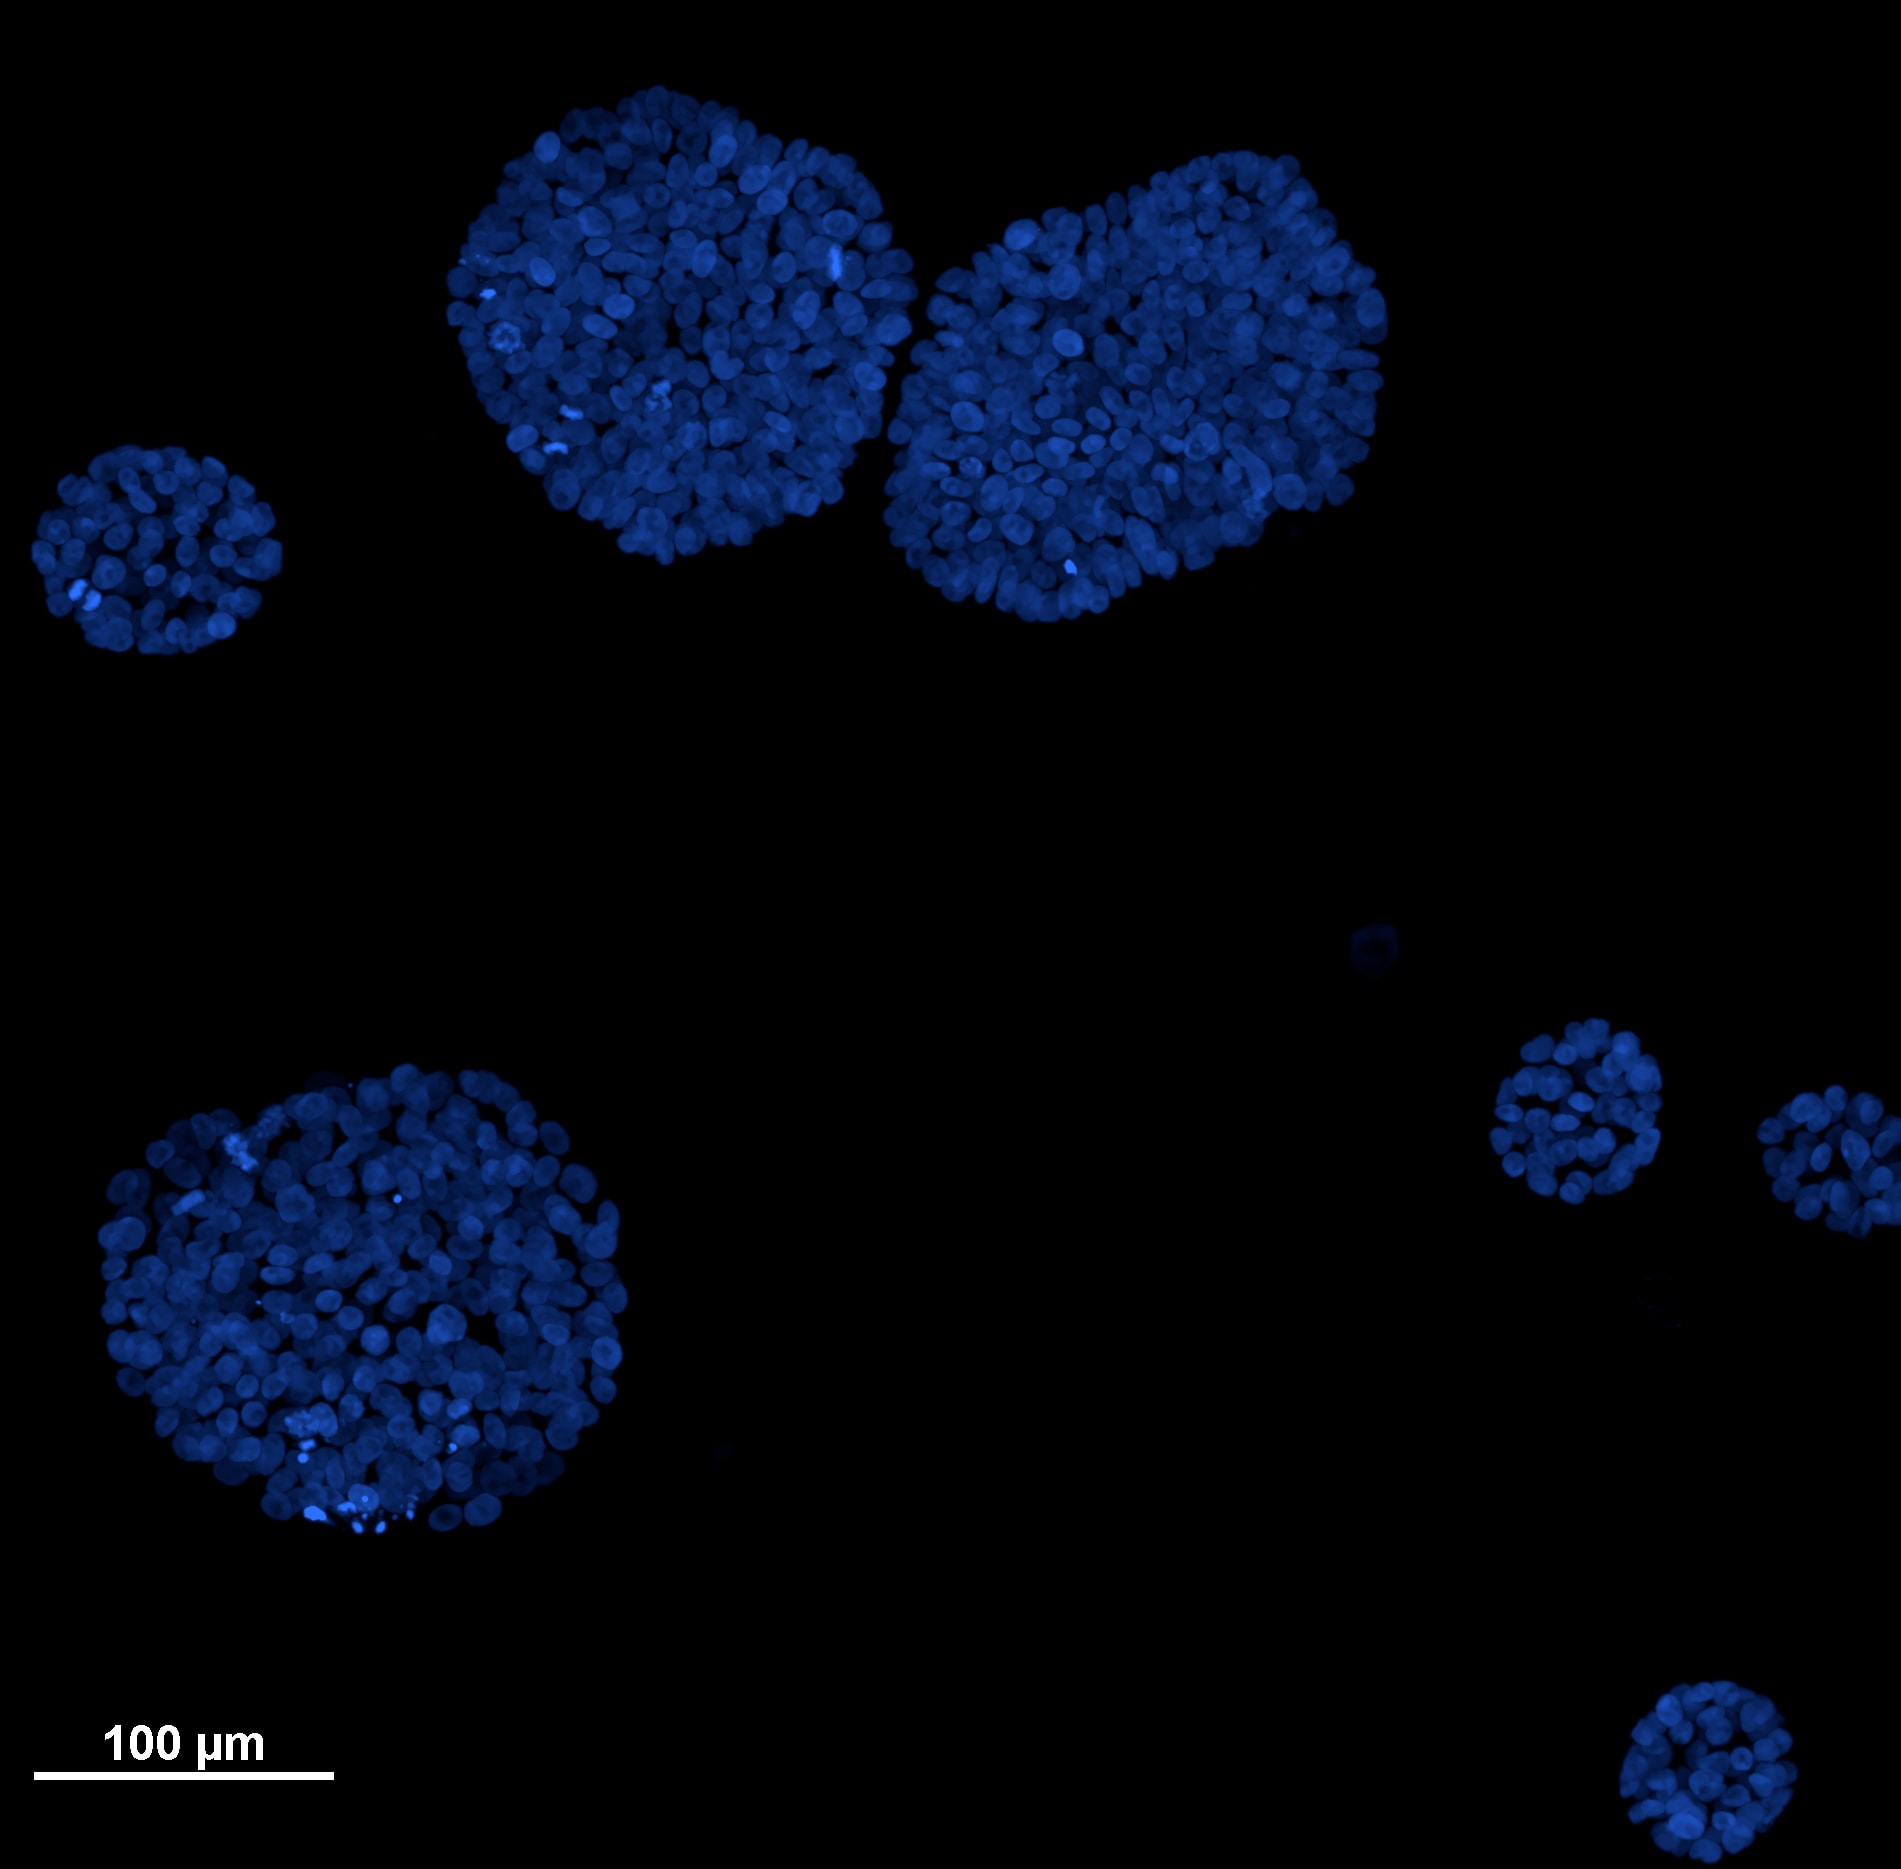

Here we show mammary epithelial cells grown in 3D. In particular, MCF-10A cells (an immortalized non-transformed human epithelial cell line derived from the breast tissue of a 36-year-old patient with fibrocystic changes) has been grown for 7 days in culture medium HUMEC with 2% Matrigel (for further method details see Debnath et al.,Methods, 2003) and subsequently stained by Hoechst 33342 to visualize nuclei. Under these growth conditions, 3D organized and polarized acinar units have been formed starting from single cells seeded on a basement membrane gel. Noteworthy, in literature it has been reported that this 3D epithelial culture method helps to recapitulate numerous features of breast epithelium in vivo, such as the formation of acini-like spheroids, cell polarization, and, in some cases, the production of milk proteins. Moreover, it provides an important tool to characterize how cancer genes disrupt glandular architecture during carcinoma progression.

Acini images have been acquired with a Nikon Ti2 inverted microscope equipped with CrestOptics confocal spinning disk X-Light V3, camera Photometrics BSI (6.5 um pixel size) and Celesta laser source (Lumencor). In Figure A, we shown a maximum intensity projection of a Z stack acquired with a 20x objective (Nikon, Plan Apo Lambda NA 0.75) displaying different size and shapes of acini in culture and a movie with 3D acini reconstruction. Focusing on the 3D structures of interest, we used a 60x objective (Nikon,Plan Apo Lambda 60X, Oil, NA 1.4) to better appreciate cellular organization along the Z axis (Figure B_1) and in 3D volume and orthogonal views (Figure B_2). Finally, we were interested in morphological nuclei analysis and by thresholding based on nuclei fluorescence intensity it was possible to identify each single object (nucleus; Figure C) and consequently perform measurements such as nucleus volume, orientation, sphericity, elongation (data not shown).

Figure A:

maximum intensity projection and movie with 3D reconstruction